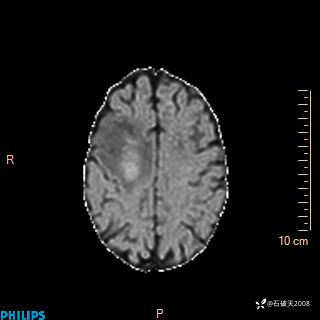

2020.11.14MR

T2

T1

FLAIR

DWI

ADC

增强轴位

增强矢状位

增强冠状位